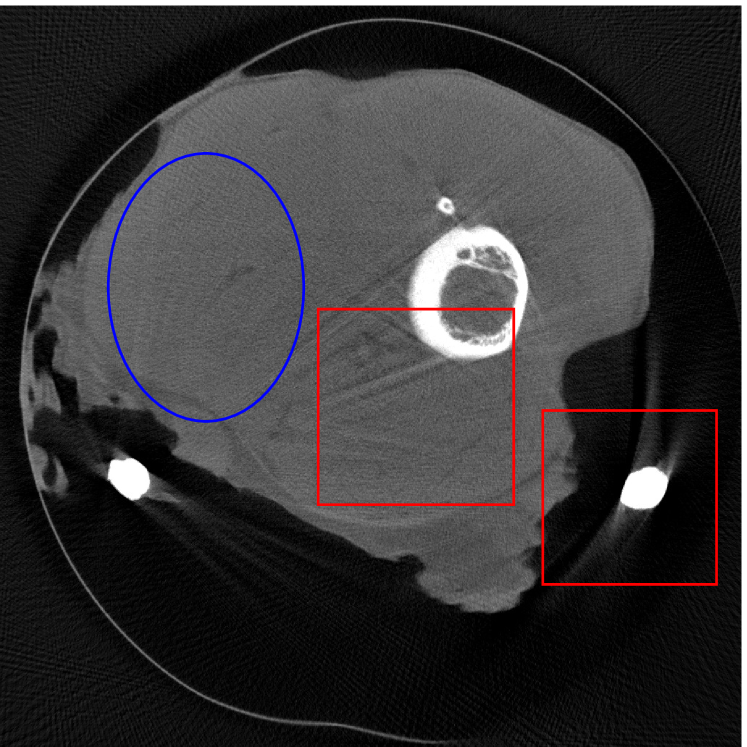

4.2 Numerical experiments: real data

We perform a CT scan of a chicken leg placed in a disposable cup (Figure 10(a)). We first scan the chicken leg without metals (Figure 10(b)) to create a reference image using FBP algorithm. Then, we place two steel thread nails on each side of the chicken leg and scan the subject again using the same scanning protocol (Figure 10(c)). The projection data is acquired from a MicroCT scanner equipped at the Division of Nuclear Technology and Applications, Institute of High Energy Physics, Chinese Academy of Sciences. The X-ray source is with 90 kV and 70 mA energy and the flat plane detector contains pixels. The scanning trajectory is a full circle with equally spaced views at per view. The physical size of each detector unit is . The distance from the X-ray source to the detector is . In order to conduct a 2D experiment, we choose the 512th row of the detector array.

Figure 11 shows the images reconstructed using FBP, the analysis model (2.12), the inpainting model (2.13) and the segmented image from the image obtained by (2.14). The reference image without metal implants are shown in Figure 11(a). All the images in this subsection are displayed within the grayscale interval . The segmented image shown in Figure 11(e) is used to estimate the weights needed in NMAR and the re-weighted JSR model.

Figure 12 shows a comparison between the reconstructed image from NMAR and the unweighted JSR model. Figure 13 shows a comparison between the reconstructed images from TV-FADM and the proposed re-weighted JSR model. Zoom-in views are provided in both Figure 12 and Figure 13 for a better visual assessment. As one can see that the reconstructed images from the unweighted JSR model and TV-FADM are less noisy than NMAR as indicated by the blue ellipse curve, whereas NMAR does a better job in preserving image features and suppressing metal artifacts. However, there are also new artifacts around the metal on the right as shown in Figure 12(d). The proposed re-weighted JSR model has best overall performance in terms of feature preservation, noise and metal artifact reduction.